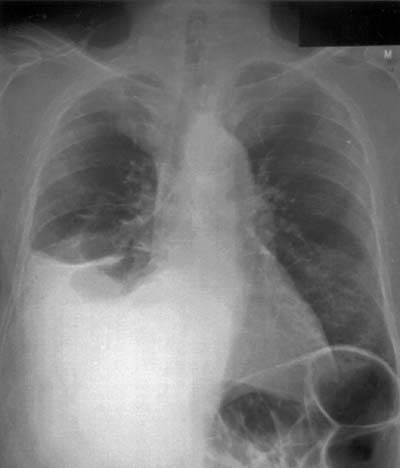

Radiological evaluation is essential to determine if a patient with MPM has potentially resectable disease. Posteroanterior and lateral chest roentgenogram (Figure 1), computerized tomography (CT scan) of the chest and upper abdomen (Figure 2), and magnetic resonance imaging (MRI) of chest have been the most widely used modalities. CT scan provides an estimate of tumor burden and extent of tumor both locally and distantly. MRI can supplement the CT scan for detection of tumor extension into the mediastinum or the abdomen. More recently, positron emission tomography (Figure 3) has been used to determine if a patient has early resectable disease based on no evidence of contralateral disease or distant metastasis. Early results are promising [6].